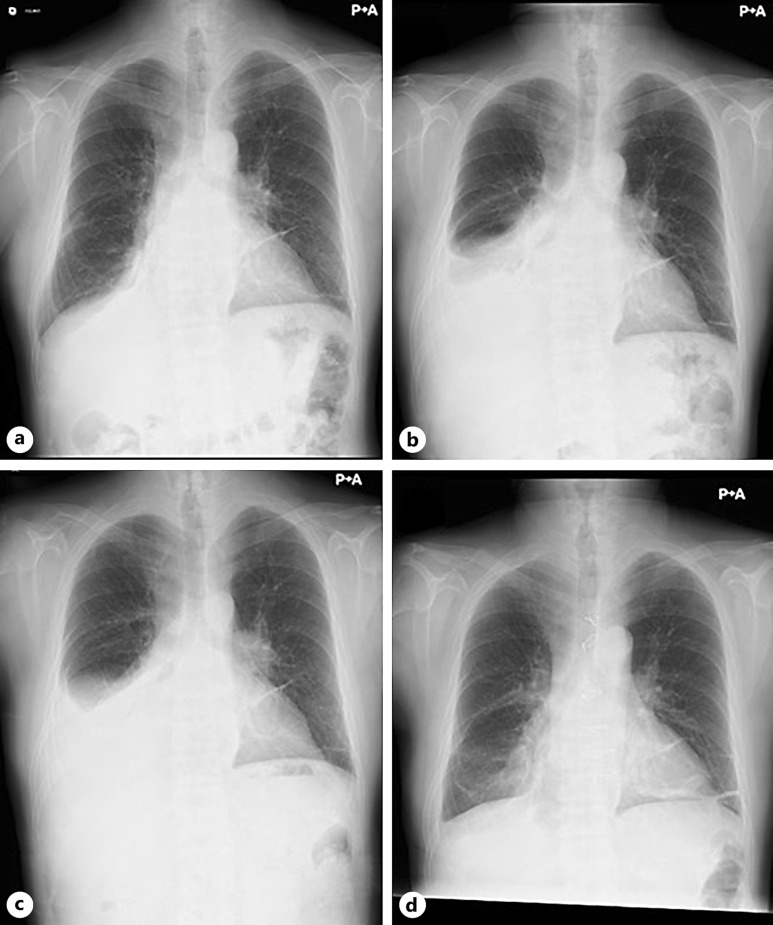

Case presentation: We report the case of a 53-year-old man on hemodialysis who developed CP with shock. His blood pressure was 55/30 mm Hg at the time of hospitalization due to presyncope. He continued hemodialysis but with some difficulty. However, right pleural effusion persisted because of impaired fluid removal by hemodialysis. Despite such severe manifestations, the distinctive clinical features of CP were lacking. By carefully evaluating the time course of computed tomography images, progressive calcification in the pericardium emerged as a significant clue. Cardiac catheterization subsequently revealed a dip-and-plateau pattern of right ventricular pressure, which led to a definitive diagnosis of CP. Soon after the diagnosis, he underwent successful surgery.

Conclusion: An important finding was that, unlike calcific lesions in the general dialysis population, the patient's calcific lesions were mostly confined to the pericardium and progressed on a monthly basis. Thus, the present case may provide deep insight into the diagnosis of CP and the management of hemodialysis patients with severe hypotension.